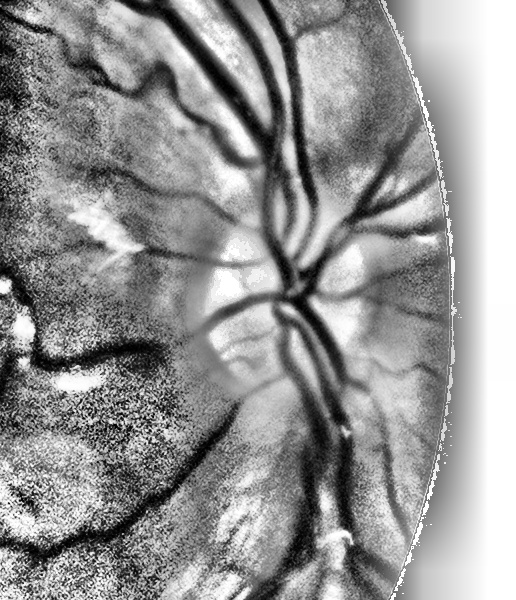

我有一个图像,我正在平衡,然后使用爪形直方图,如下所示:

self.equ = cv2.equalizeHist(self.result_array)

clahe = cv2.createCLAHE(clipLimit=100.0, tileGridSize=(8,8))

self.cl1 = clahe.apply(self.equ)我得到的结果是:

我想去掉所有的黑点,那就是噪音。最终,我试图从上面所示的图像中提取出血管,这些血管是黑色的,在这样做的时候,噪音会使提取不准确。